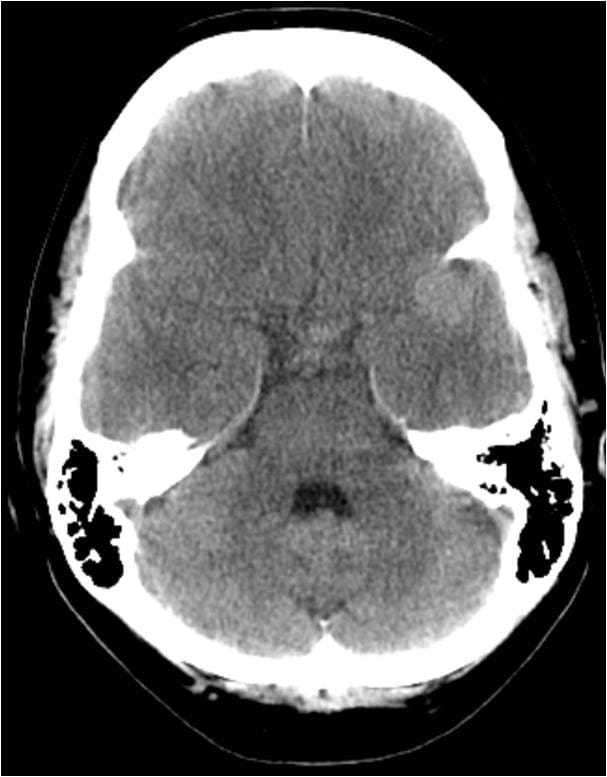

This video documents the surgical clipping of a giant middle cerebral artery aneurysm. The patient is a 56-year-old woman with a Grade I subarachnoid hemorrhage.

Supplemental photos also accompany the video below.